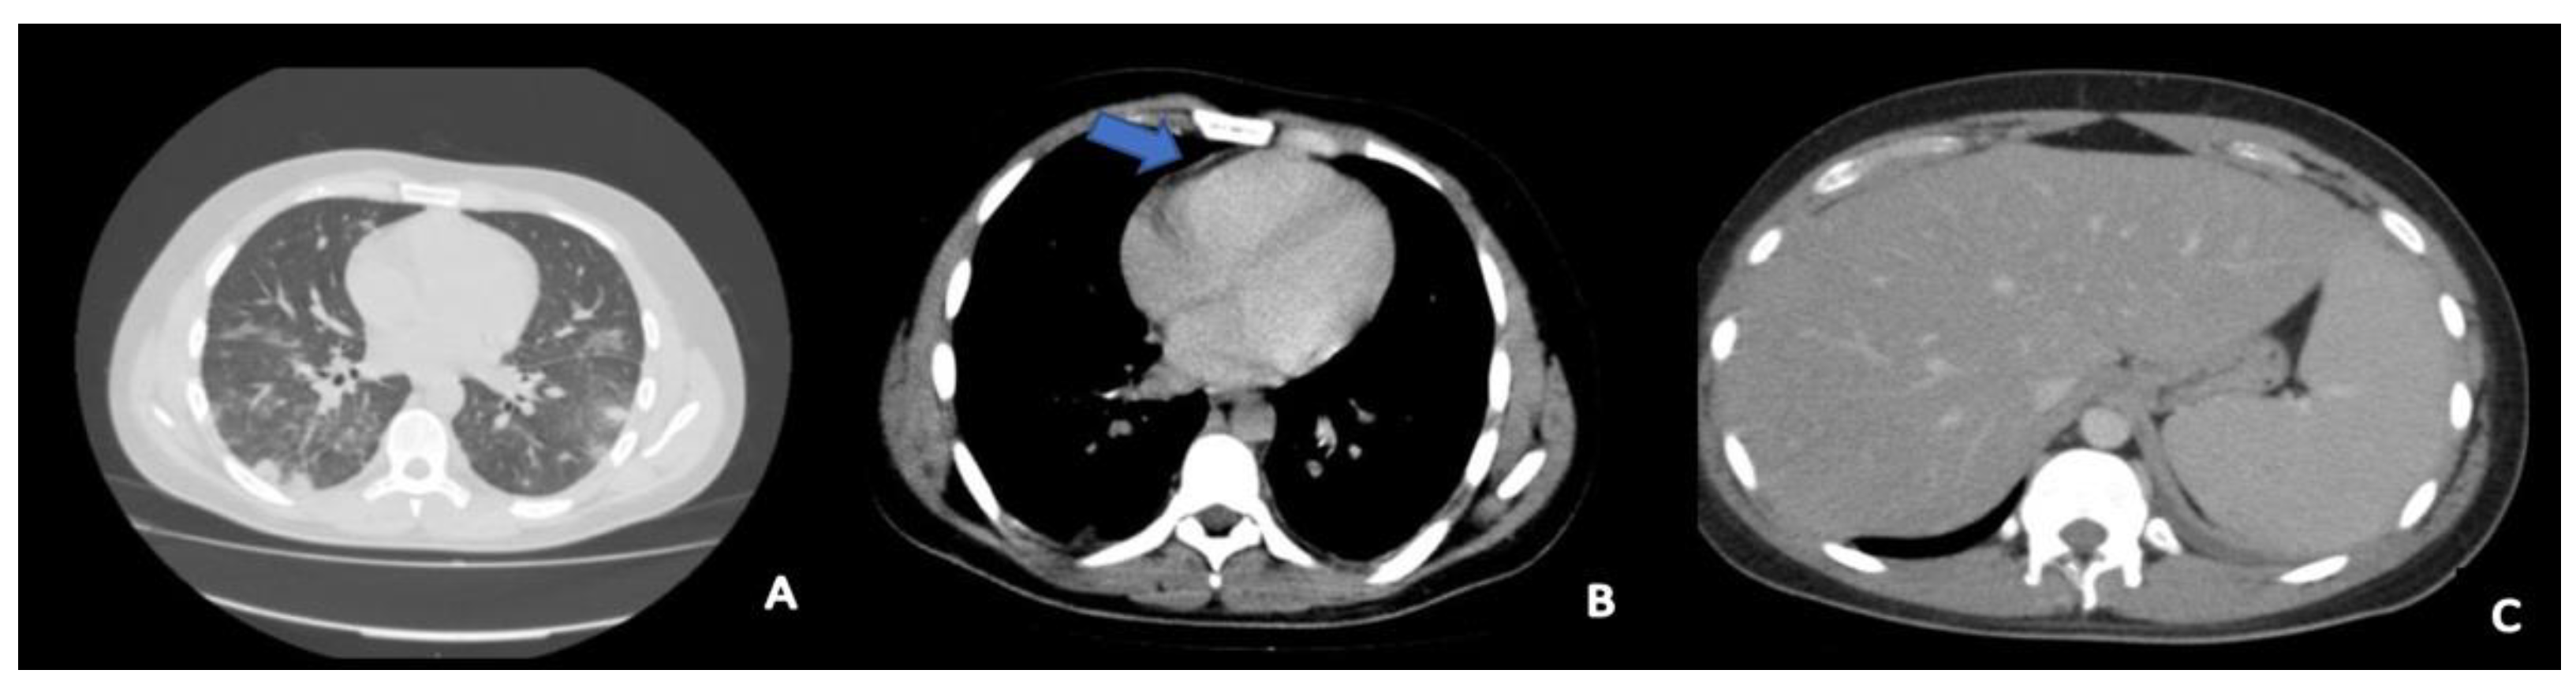

2. Case Presentation

2.2. Intensive Care Unit Management